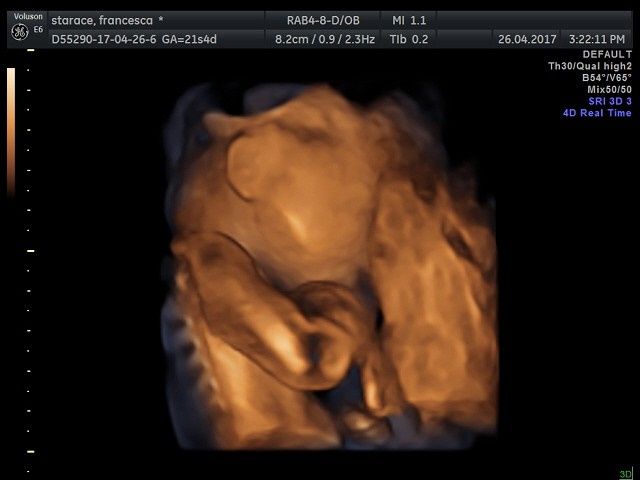

Ciao ragazze, in un attacco di insonnia vi posto le foto della morfologica in 4d di ieri๐Ÿ˜! La polpetta sta alla grande, pesa 430 gr ed รจ tale e quale al papa!๐Ÿ˜‚๐Ÿ˜‚๐Ÿ˜‚tutti questi mesi nella pancia con noi mamme, e poi sono la fotocopia dei mariti!!!๐Ÿ˜‚๐Ÿ˜‚๐Ÿ˜‚un bacio da me e e Bianca 21+5๐Ÿ’–notte!!!!

Morfologica, che spettacolo!!!! - 1